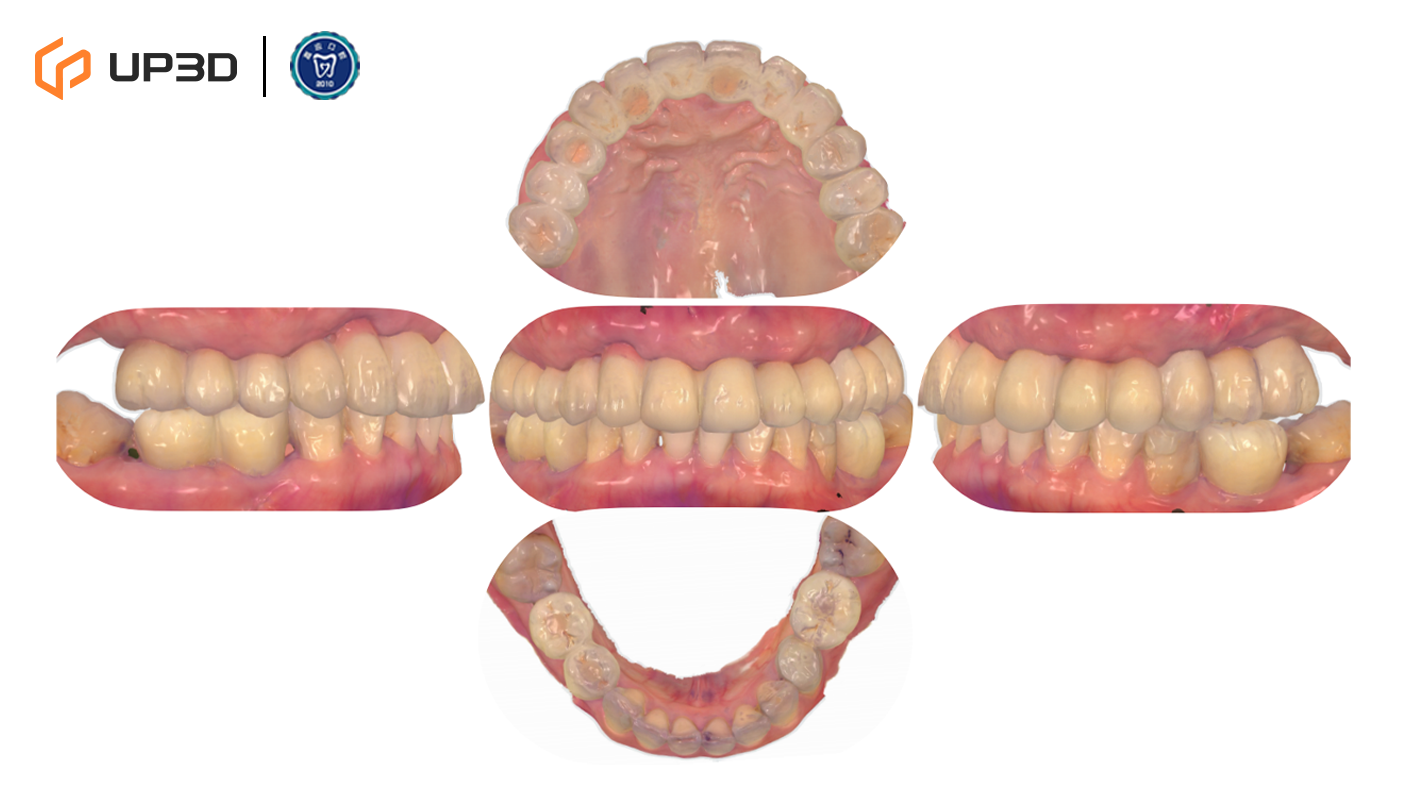

7.4 Final Delivery

After delivery, the definitive prosthesis demonstrated:

-

Balanced occlusal contacts and an esthetically pleasing profile

Appropriate hygiene access and comfortable function

A post-delivery intraoral scan was archived to establish a digital record for future comparison and maintenance

8. Outcome and Follow-Up

8.1 Post-Delivery Facial and Smile Evaluation

Frontal and profile photographs indicated:

Improved lower facial support and a more natural smile line

A more relaxed expression and improved facial proportions

High patient satisfaction with both esthetics and function